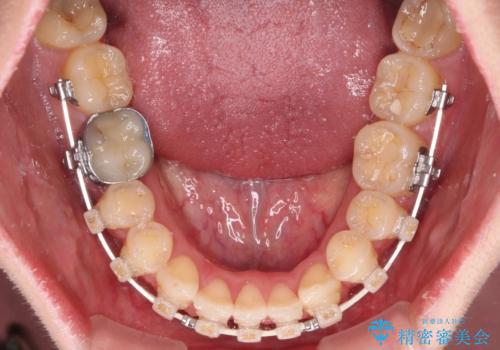

- 矯正装置

- 審美装置

マウスピース矯正は自己管理が煩わしいとのことで、ワイヤー装置にて矯正治療を行うこととしました。